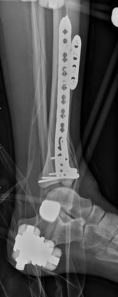

Complex Tibial Shaft Fracture: Plate Fixation for Plafond Extension

We review everything you need to understand about Complex Tibial Shaft Fracture: Plate Fixation for Plafond Extension. A **tibial shaft fracture** extending into the plafond is a complex injury characterized by a displaced, often multifragmentary break in the midshaft of the tibia that also involves the ankle joint's articular surface. These severe fractures commonly require immediate fasciotomy if compartment syndrome is present, followed by open reduction and internal fixation (ORIF) to restore anatomical alignment and joint function.

When a diaphyseal fracture propagates into the distal articular block, the injury transcends the typical treatment algorithms reserved for isolated tibial shaft fractures. Intramedullary nailing, the gold standard for diaphyseal fractures, becomes fraught with complications such as articular malreduction, propagation of intra-articular fracture lines, and inadequate distal fixation. Therefore, plate fixation—often utilizing minimally invasive percutaneous plate osteosynthesis (MIPPO) techniques—emerges as the primary definitive treatment modality. In the setting of an AO/OTA 43C3.3 fracture, where the articular surface is multifragmentary and completely dissociated from the diaphysis, the surgeon must meticulously reconstruct the joint surface before bridging the diaphyseal segment.

Once the articular block is reconstituted, the plate acts as a bridging construct across the zone of metaphyseal and diaphyseal comminution. Locking plate technology is paramount in this region. The locking screws provide angular stability, functioning as an internal fixator that does not rely on friction between the plate and the underlying periosteum. This preserves the extraosseous blood supply, which is vital for secondary bone healing via callus formation. The working length of the plate must be optimized to allow for micromotion at the fracture site, promoting robust enchondral ossification while preventing catastrophic hardware failure.

The distal portion of the plate is secured to the reconstructed articular block. It is imperative that the distal locking screws are placed parallel to the joint space, forming a rigid subchondral raft that supports the articular cartilage. Fluoroscopy is utilized extensively to ensure no screws have penetrated the joint. Once the distal block is secured to the plate, the diaphyseal segment is aligned. Length, alignment, and rotation are restored using manual traction or the femoral distractor. The proximal portion of the plate is then secured to the diaphysis using a combination of non-locking screws (to pull the bone to the plate) and locking screws (to create a fixed-angle construct). The working length of the plate is maximized by leaving several screw holes empty over the zone of comminution, promoting secondary bone healing.